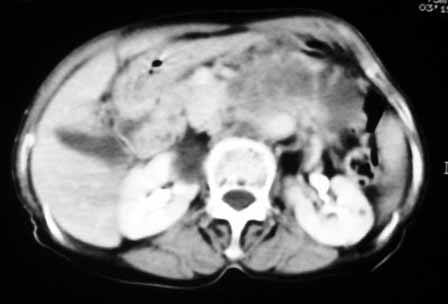

以下是引用天南地北在2007-4-30 17:42:00的发言:[br]增强扫描显示腹主动脉给包绕、推移。肿块不规则强化,[br]修正我在平扫的诊断[br]支持考虑:间叶源性肿瘤可能性大

以下是引用余辉在2007-4-30 18:01:00的发言:[br]病灶前方的条状增强影是什么?若是胰腺,位置似乎有点低,若是十二指肠,似乎又不诫该是那样强化,姑且将其看作胰腺吧,那么考虑来源于胰腺粘液囊腺瘤可能性大,其次考虑来源于肠系膜或者后腹膜的肿瘤如平滑肌肉瘤,异位嗜铬细胞瘤及淋巴瘤等。